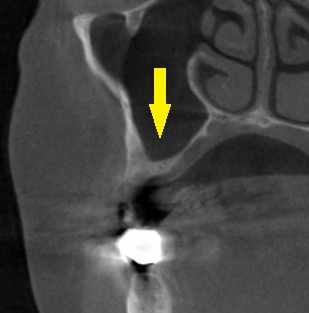

CTを撮影してみると、骨の高さが3mm程しかありませんでした。

サイナスリフトという、やや大きな骨造成手術を行う方が確実に骨を増やせるのですが、大きな手術は怖いとのことでした。

そこで、ワイド径のインプラントを使用して、骨造成術を回避する方法を提案させていただきました。

これならと同意いただけましたので、本日、直径6mm、長さ7mmのインプラントを人工骨を用いることなく埋入しました。

下の写真、2段目が手術前、3段目が手術後のCTです。